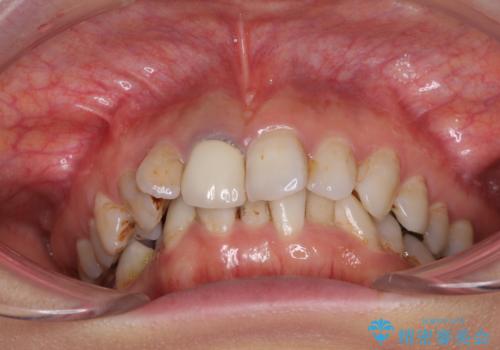

- 前歯の歯並びやむし歯治療の跡、奥歯の銀歯を気にして来院された患者様です。

インビザラインによる矯正治療の後に虫歯や銀歯をセラミックにて補綴することとしました。